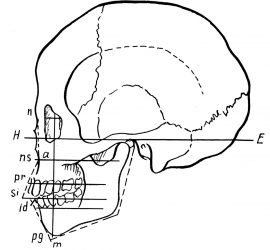

Франкфуртская горизонталь

Франкфуртская горизонталь — немецкая горизонталь, введена как антропологическая измерительная плоскость на антропологическом конгрессе во Франкфурте-на-Майне в 1884 г., проходит через верхний край наружного слухового прохода и самую глубокую точку глазницы. В клинике ориентирами являются: верхний край козелка уха и пальпаторно — нижний край орбиты.